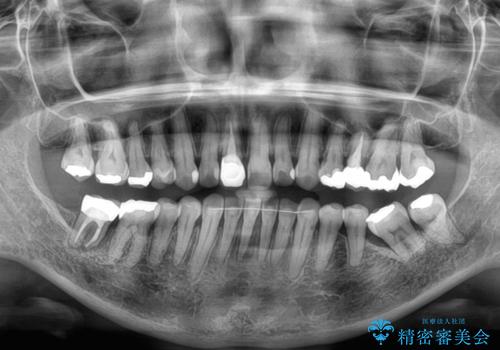

痛みがなくなり歯列が整ったことで、残っている銀歯も気になり始めているようです。

マウスピース生活に疲れてしまったとのことで、暫くお休みをしてから銀歯の治療を再開していく予定です。